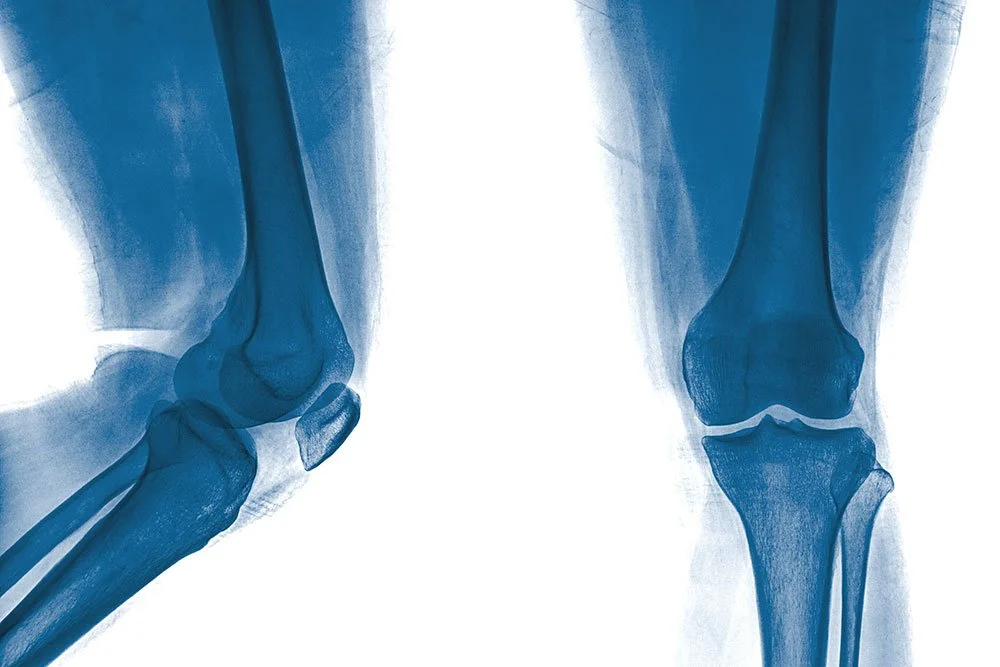

Bilateral knee arthritis presents a unique challenge. When only one knee is affected, the treatment path is usually straightforward. But when both joints are significantly worn down, patients face a more complex decision about timing and strategy for double knee replacement.

A double knee replacement can be performed in two different ways.

In a simultaneous procedure, both knees are replaced during the same surgery under one anesthetic. In a staged procedure, the surgeon replaces one knee first, allows it to heal, and schedules the second surgery several months later.